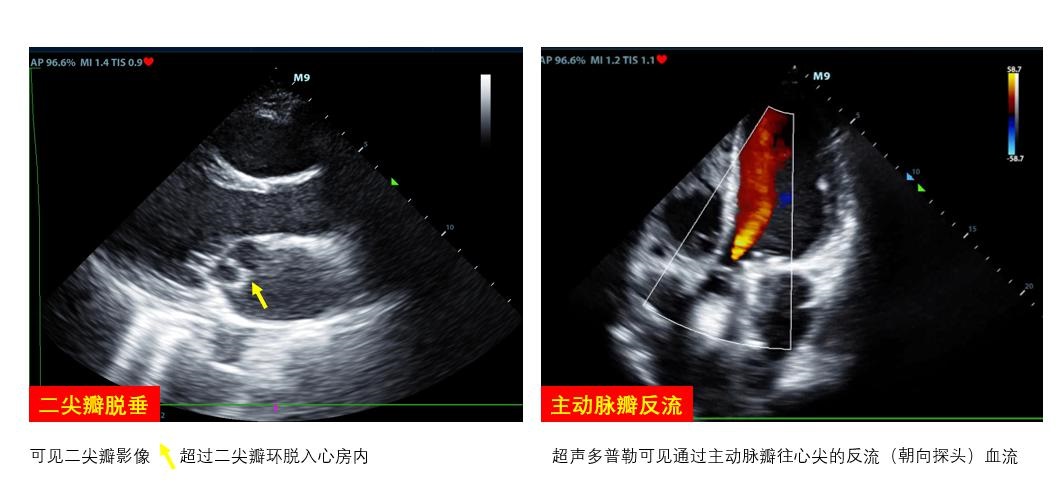

D、瓣膜通过观察瓣膜开合节律和频率评估瓣膜功能及心律失常,二尖瓣开放程度(EPSS)协助评估左心室收缩功能。瓣膜区彩色多普勒超声可评估瓣膜反流、狭窄情况。重度主动脉瓣反流如不能短期内进行外科干预者影响VA-ECMO实施效果(图 6右)。室壁无增厚的右室扩张合并急性三尖瓣、肺动脉瓣反流提示可能存在肺动脉栓塞。呼吸衰竭肺水肿者检查有无二尖瓣脱垂(图 6左)、重度二尖瓣反流。不管是原发还是继发严重瓣膜问题,均可能会在ECMO实施时影响支持效率,因此,建议在ECMO准备阶段筛查瓣膜功能。

| 图 6 可能影响ECMO效果的瓣膜病变 |